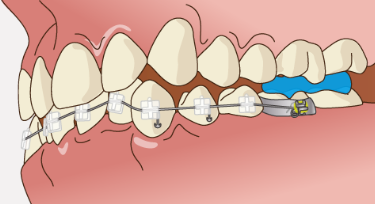

難しいのは前歯だけでなく奥歯の高さを大きく変える必要があったり、歯の根の角度を精密にコントロールする必要があるケースです。

・奥歯が低すぎて噛み合わせがズレているため、奥歯を数ミリ単位で引っ張り出す必要があるケース

最新のインビザライン(G8システム以降)は、バイトランプやスマートフォースといった機能により、以前よりも奥歯の挺出や歯の角度コントロールが得意になりました。

しかし、大きな歯の移動や歯根ごと角度をしっかり立て直すような複雑な動きは、依然としてワイヤー矯正の方が適していることも多いです。

ワイヤーは歯を三次元的にコントロールできるため、立体的な動きや細かな微調整に強いのです。